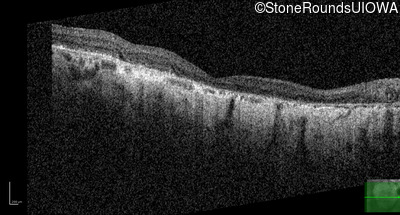

Highlighted Images

Age at visit: 55 years

Age at visit: 56 years

Age at visit: 57 years

Age at visit: 57 years (Visit 2)

Age at visit: 57 years (Visit 3)

Age at visit: 57 years (Visit 4)

Age at visit: 58 years

Age at visit: 58 years (Visit 2)

Age at visit: 59 years

Age at visit: 59 years (Visit 2)

Age at visit: 60 years

Age at visit: 60 years (Visit 2)

Age at visit: 61 years

Age at visit: 62 years

Age at visit: 62 years (Visit 2)

Age at visit: 63 years

Age at visit: 63 years (Visit 2)

Age at visit: 65 years

Age at visit: 66 years

Age at visit: 67 years